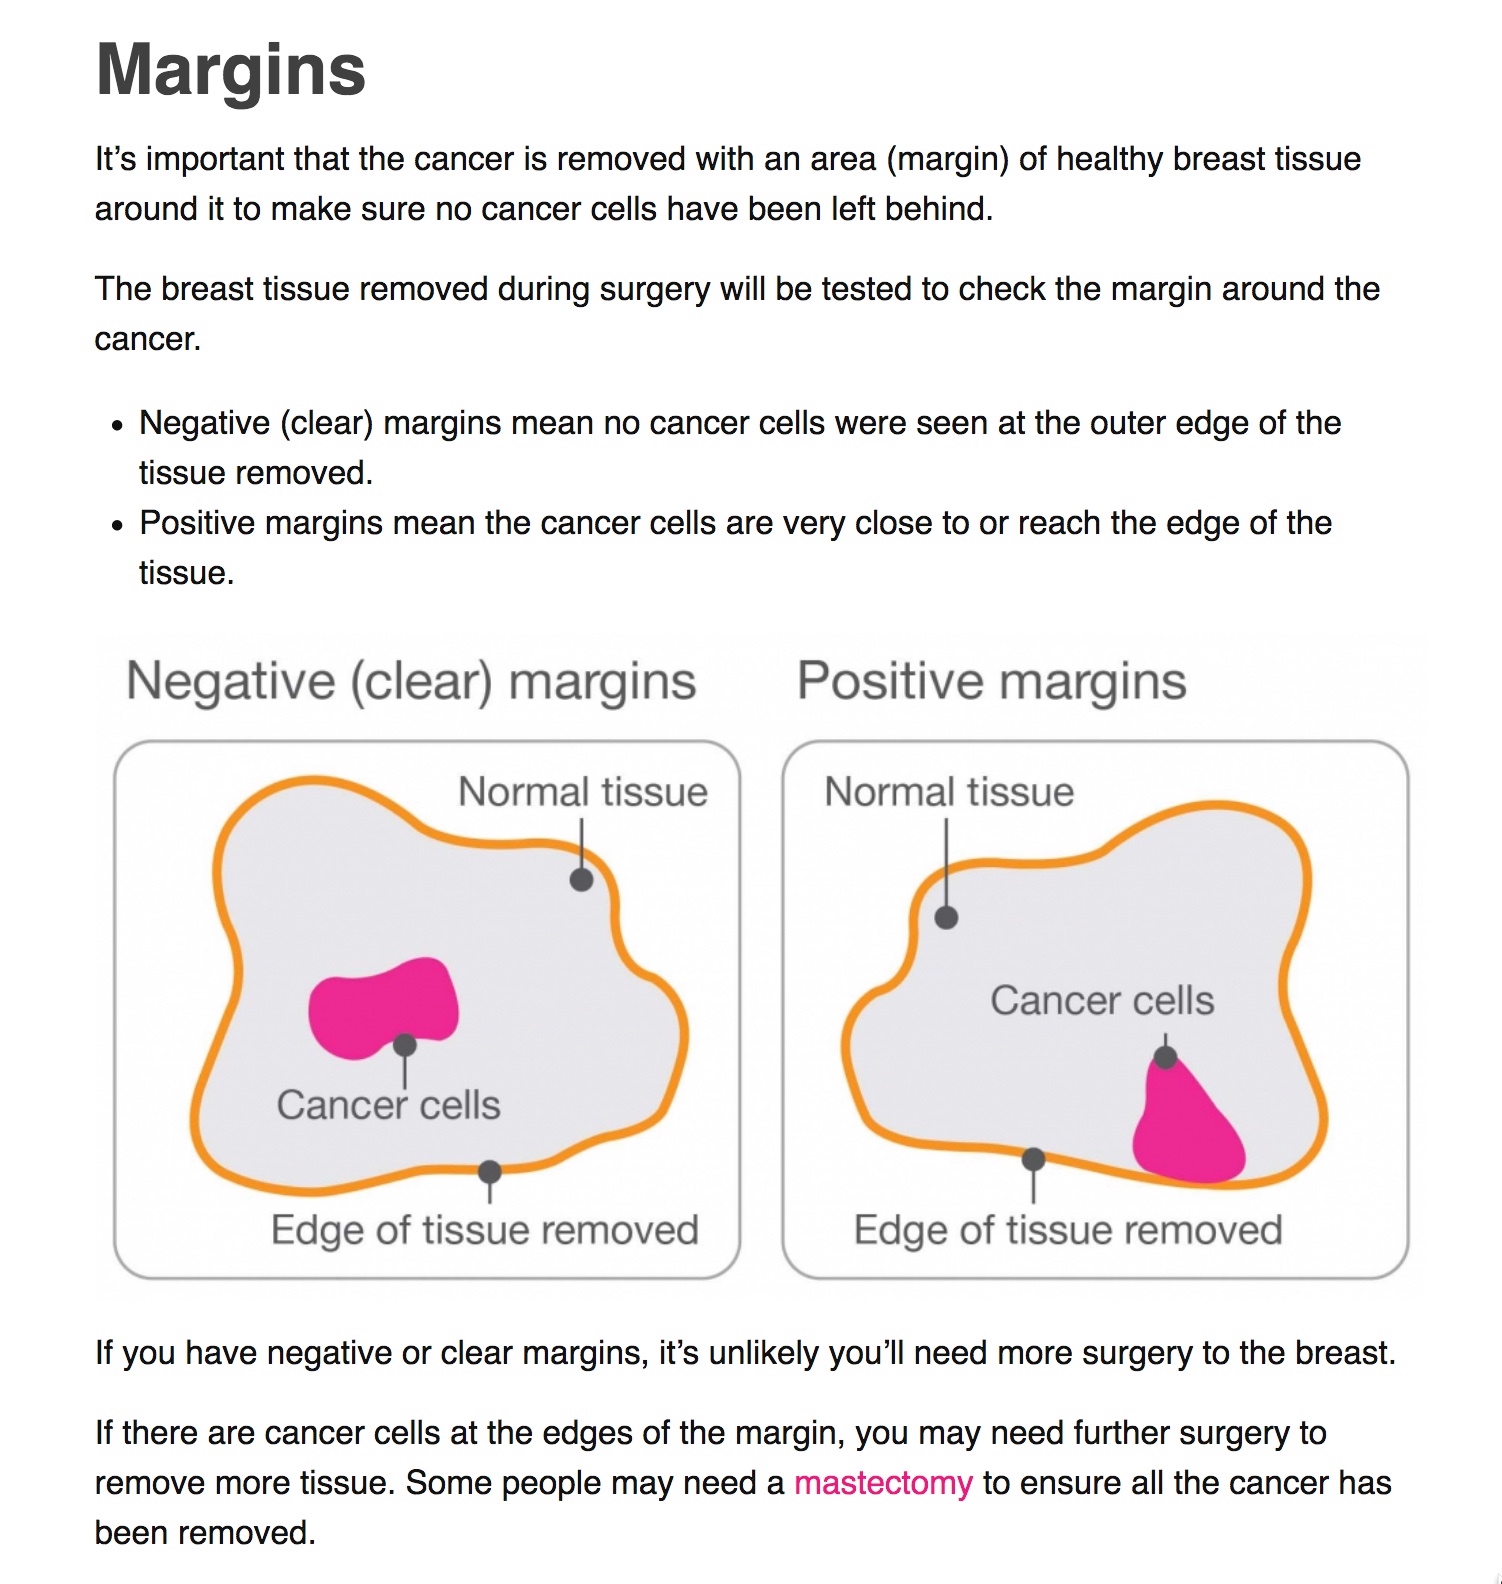

Breast-conserving Surgery – Torbay And South Devon NHS Foundation Trust

www.torbayandsouthdevon.nhs.uk

community.macmillan.org.uk

community cancer breast margins macmillan online results

Guide To Understanding Surgical Margins | KUBTEC

www.kubtec.com

What Do Margins Mean In Breast Cancer / Resection Margin Wikipedia

dcis margins breastcancernow carcinoma ductal situ tumor stage